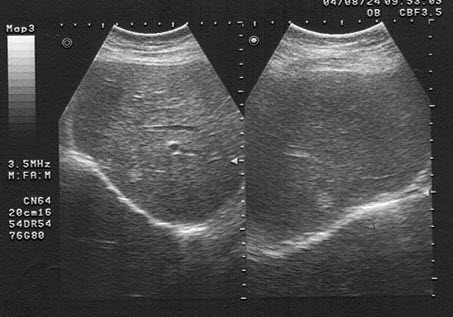

女,40岁,有时右上腹隐痛2年余。结合超声声像图,最可能的诊断为()